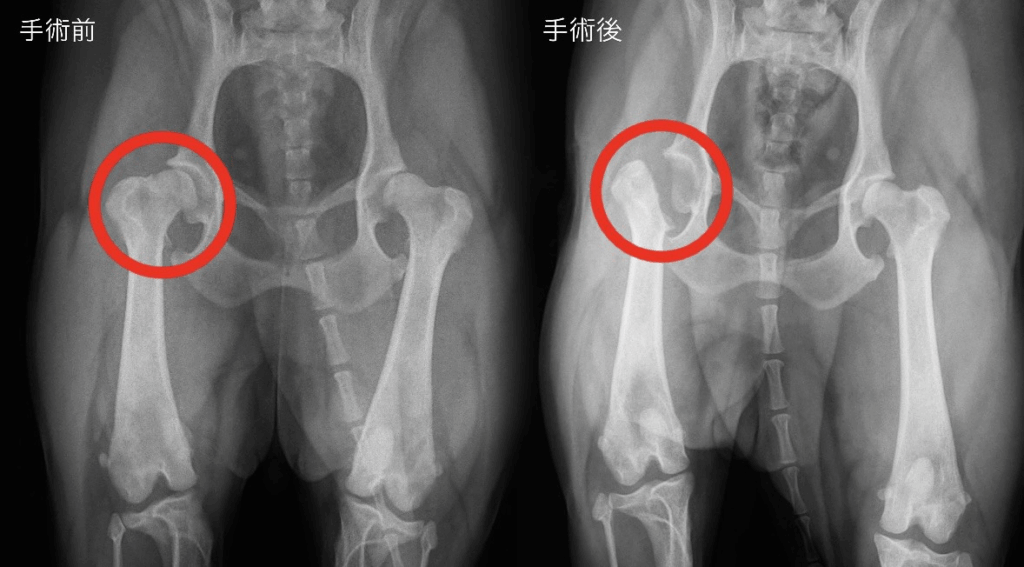

ケース2:とっても元気なわんちゃんがレントゲン検査で関節炎を発見

こちらのわんちゃんも普段から明るく元気いっぱい。

お散歩も大好きで、飼い主さんも「痛がっている」様子は感じていなかったそうです。

年齢的にもまだ若く、「健康診断は念のため」という感覚で来院されました。

ところが、健康診断でレントゲン検査を行ったところ、関節炎の初期症状が見つかりました。

関節炎は、初期の段階では「目に見える痛み」がほとんどなく、飼い主さんが気づきにくい病気のひとつです。

わんちゃん自身も痛みを隠して、普段通りに振舞うため、発見が遅れるケースも多くあります。

今回見つかったのも、まさに「症状が出る前の段階」。

早いタイミングで異常がわかったため、そのまま整形の専門外来受診してもらい詳しい検査を受けて頂きました。

診断の結果、手術を行った方が今後の生活の質を保てると判断され、適切なタイミングで手術を実施。

無事に手術を終えて退院後は、痛みのコントロールも良好で、現在は元気にお散歩も楽しめています。

「症状がなくても、早めに見つけられれば治療も選択肢が広がり、将来の痛みや歩行トラブルを防ぐことにつながる」そのことを改めて実感したケースでした。